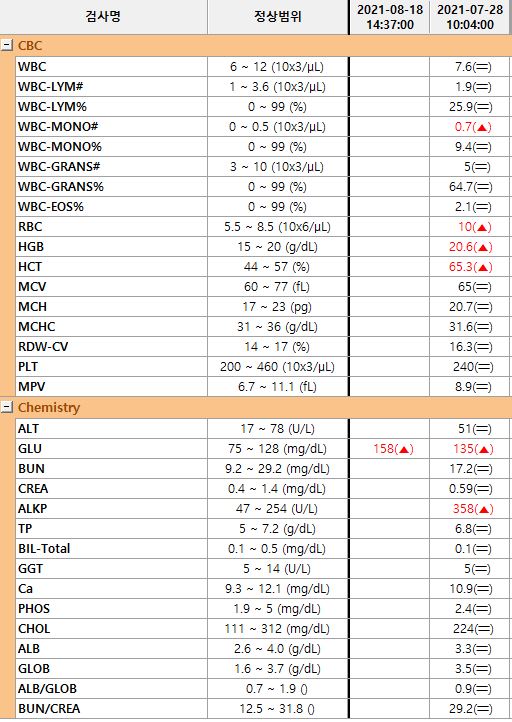

수술전검사(기본신체검사,흉복부xray,혈액검사)*흉복부x선검사

- 혈액검사(혈구검사, 혈청 화학검사) 혈당관리도 잘 되어 있는 상태이며 별다른 이상이 없으므로 충분한 수액처치 후 수술을 시행하였습니다.

당뇨병인데 수술이 가능합니까?네, 당연히 가능하죠혈당 관리가 잘 되고, 눈에 다른 문제가 없는 경우에는 다른 자녀와 마찬가지로 마취 전 검사를 실시하고 수술을 실시합니다.